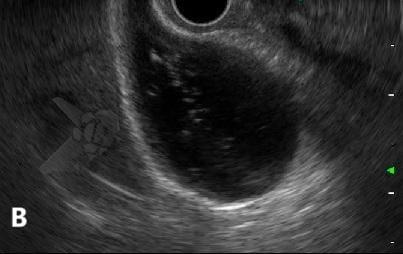

El polvo biliar se ha definido como una imagen hiperecoica flotante, sin sombra acústica posterior, observada o acentuada tras la palpación abdominal³. Se trata, por lo tanto, de la misma entidad ecográfica que, en Brasil, tradicionalmente se ha denominado “microlitiasis”, pero que no se ajusta a la definición de consenso internacional de microlitiasis y terminó siendo prácticamente ignorada por el consenso, o, en algunos casos, incluida a la fuerza bajo el término “lodo biliar”.

El polvo biliar se definió como una imagen hiperecoica flotante, sin sombra acústica posterior, observada o acentuada tras la palpación abdominal — una entidad ecográfica anteriormente denominada “microlitiasis” o “microcálculo” en nuestro medio. La introducción de este término busca conciliar los hallazgos ecográficos frecuentemente observados en la práctica diaria con las definiciones establecidas por el Consenso Internacional de 2023.